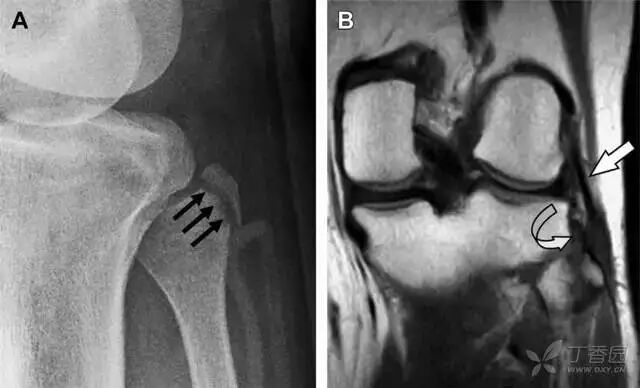

前交叉韧带胫骨髁间嵴撕脱骨折

前交叉韧带撕脱骨折常发生在胫骨髁间嵴(图 1)。这种骨折在青少年中常见,但在成年人中也并不像大家想象的那么少见。

图 1 摩托车事故患者前交叉韧带撕脱性骨折。A 正位片示胫骨髁间嵴底部骨折(箭头),注意别把这个骨折碎片错认为关节内结构。B 侧位片示胫骨上方可见一细长型骨折碎片(椭圆)。C MRI 矢状位 T2 加权像示前交叉韧带附着于撕脱的骨折碎片上(箭头),注意周围存在骨髓水肿和积脂血征(空箭头)

股骨外侧髁凹陷征(图 2)

图 2 扭伤后的股骨外侧髁凹陷征。A 侧位片示股骨外侧髁凹陷。B MRI 矢状位 T2 加权像示股骨外侧髁及胫骨后外侧骨挫伤(空箭头)。胫骨近端随着后交叉韧带撕裂发生移位,露出外侧半月板的后角(弧形箭头)